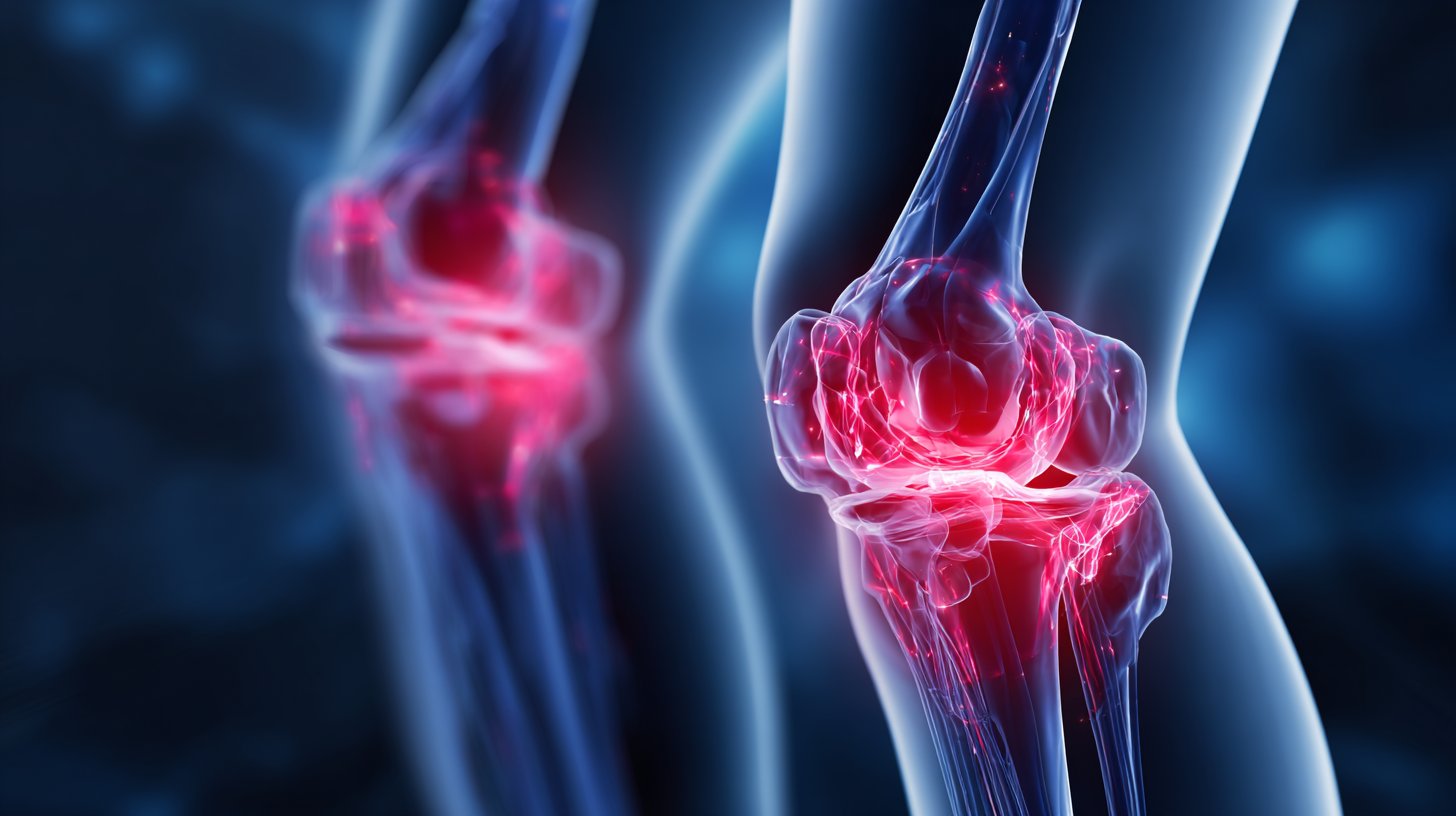

Hip arthrosis, commonly known as osteoarthritis of the hip, is a degenerative joint disease that affects millions worldwide. According to the Global Burden of Disease Study, hip osteoarthritis ranks among the top ten causes of disability in adults over 50 years. This condition is characterized by the gradual wear and tear of cartilage, leading to pain, stiffness, and decreased range of motion. By age 65, approximately 50% of individuals experience some level of hip discomfort, emphasizing the urgent need for effective management strategies.

Hip arthrosis, also known as osteoarthritis of the hip, is a degenerative joint disease that often manifests with key symptoms, making early diagnosis crucial for effective management. Typical signs include hip pain, stiffness, particularly in the morning, and reduced range of motion. According to the Arthritis Foundation, approximately 27 million Americans are affected by osteoarthritis, highlighting the commonality of hip-related joint issues. As the cartilage wears down over time, these symptoms can become increasingly pronounced, significantly impacting mobility and quality of life.

Seeking treatment for hip arthrosis should be considered when symptoms escalate beyond manageable levels or adversely affect daily life. The American Academy of Orthopaedic Surgeons emphasizes that an active lifestyle, recognized as essential for joint health, may become untenable with advanced hip arthrosis. Timely intervention can include non-surgical methods such as physical therapy, pain relief medications, or corticosteroid injections, and in severe cases, surgical options like hip replacement may be recommended. Understanding when to seek professional advice can lead to more effective management strategies and improved mobility outcomes.